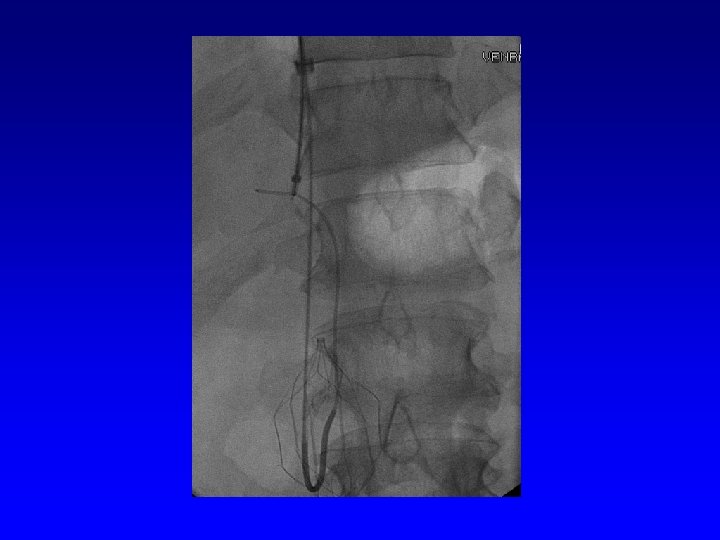

IVC Filter Removal Straight forward and Complex

Removal of an “Intravascular Foreign Body” Straight forward Loop snare Grasping device Complex Multiple devices used including angioplasty balloons, bronchoscopy forceps, and the“in situ” snare technique.

Retrieval with a snare and a long sheath or guiding catheter Günther Tulip (Cook) Celect (Cook) Opt Ease (Cordis Endovascular) Option (Angiotech) G 2 X, Eclipse, Meridian (Bard)